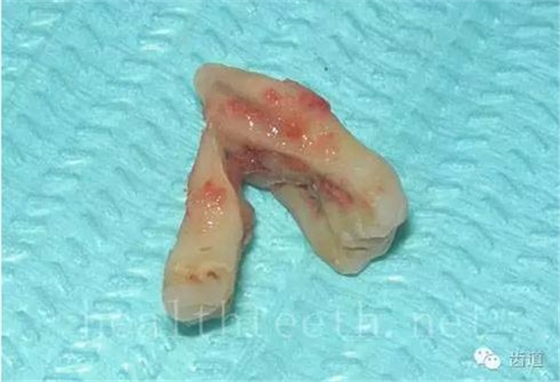

長期戴活動義齒不當或是戴不良修復(fù)義齒造成的口腔粘膜潰瘍,應(yīng)該引起高度警惕,因為這種潰瘍?nèi)菀装┳?/span> 黑毛舌 舌息肉,該患者同時伴有胃、食管息肉,后來看內(nèi)科了,具體情況不詳 四、孩子的牙齒問題 乳牙未退,牙根穿出牙齦對上唇粘膜造成刺激 乳牙滯留,也是孩子在退牙過程中最容易遇到的問題 五、牙齒發(fā)育上的問題 變色牙 氟斑牙 釉質(zhì)發(fā)育不全 四環(huán)素牙 牙神經(jīng)治療后的牙齒變色 10歲孩子剛剛萌出的牙齒變色 2、埋伏牙 左上乳3滯留,恒3未見萌出,曲面斷層片顯示牙齒埋伏 通過CT片確定埋伏牙齒具體的位置,顯示距離左側(cè)上頜竇很近,偏唇側(cè),這為手術(shù)定位提供了方便 手術(shù)中切斷、完整拔出,未損傷上頜竇 其他埋伏牙 3、多生牙 病例1 病例2 病例3,同時多生兩顆牙齒 4、各種畸形牙 畸形過小牙 融合牙:恒牙和乳牙都可以發(fā)生融合的情況(兩顆牙齒長在了一起) 畸形中央尖:在牙齒的中央,兩個牙尖之間又多長出一個牙尖,由于進食的磨耗很容易造成磨穿,神經(jīng)就會與外界相通,出現(xiàn)牙髓炎的癥狀 六、牙齒的外傷 牙冠折斷 牙根折斷 烤瓷牙打樁修復(fù)后牙根折斷 外傷后牙齒的全脫位,應(yīng)該保留牙齒盡早做再植手術(shù) 七、牙齒的慢性損傷 牙頸部楔狀缺損 牙冠劈裂及完整拔除后的情況 牙根縱裂及拔除后的情況 牙隱裂,牙齒表面有肉眼看不到的裂紋,細菌通過其進入牙髓,容易出現(xiàn)牙髓炎癥狀,嚴重可以造成牙齒的劈裂 這是一位來中國學(xué)習(xí)的俄羅斯大學(xué)生的牙齒,已經(jīng)做過了根管治療,牙齒咬合面有隱裂,通過鋼絲結(jié)扎固定,做鑄造金屬冠修復(fù)。 八、牙髓炎、根尖周炎 下面圖片都是慢性根尖周炎的病例,有了齲齒,進一步發(fā)展就是牙髓炎,如果此時沒有得到及時的治療,疾病會逐漸發(fā)展破壞到根尖的骨質(zhì),將骨質(zhì)破壞后就在牙齦上出現(xiàn)一個膿瘺,此時患者不再感覺到牙齒的疼痛了,往往忽視了治療,但是這種不痛并不是疾病好轉(zhuǎn)了,而是因為疾病的炎性滲出得到了引流,這個膿瘺會出現(xiàn)有時候變大了,有時候又變小了,但是如果不治療是不會自己愈合的,只有經(jīng)過完善的根管治療后才有好轉(zhuǎn)的可能,但是在疾病的治療中時間是起決定作用的,時間拖得越晚,好轉(zhuǎn)的可能性越小,經(jīng)過根管治療后如果膿瘺還是沒有消失,就需要做根尖刮治術(shù),如果仍然沒有好轉(zhuǎn),就只能做根尖切除術(shù)了,這對牙齒的穩(wěn)固是不利的。下面圖片中在膿瘺中插入了一個牙膠尖,是我們做根管充填用的材料,是非常軟的,就是在口腔牙齦瘺管的地方插進去,通過拍牙片可以清晰地看到它到達的位置,從而確定發(fā)病的牙齒,此處是為了讓大家看得更清楚。 門牙兩個膿瘺 烤瓷牙修復(fù)后牙齦出現(xiàn)兩個膿瘺,插入牙膠尖,牙片顯示牙膠尖到達的位置就是根尖炎癥的位置,根尖骨質(zhì)密度降低(發(fā)黑的地方) 牙齒根尖膿瘺,治療前、中、后的圖片對照,完善根管治療后膿瘺明顯消失了 牙髓炎和根尖炎治療的關(guān)鍵就是根管治療 合格的根管充填治療 不良的根管充填治療 九、關(guān)于智齒(第八顆牙) 四顆長不出來的智齒 智齒反復(fù)發(fā)炎造成的頰瘺,膿腫切開引流后面部會留疤 智齒造成的頜骨囊腫,手術(shù)切除后需要植骨 十、各種錯合畸形 開合 深覆合 深覆蓋,上頜前突 反合(地包天) 牙齒排列擁擠 來源:牙醫(yī)愛看的 KQ88口腔醫(yī)學(xué)網(wǎng)